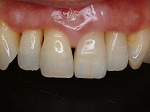

◆オールセラミック修復

~修復後~

オールセラミック修復

~修復後拡大~